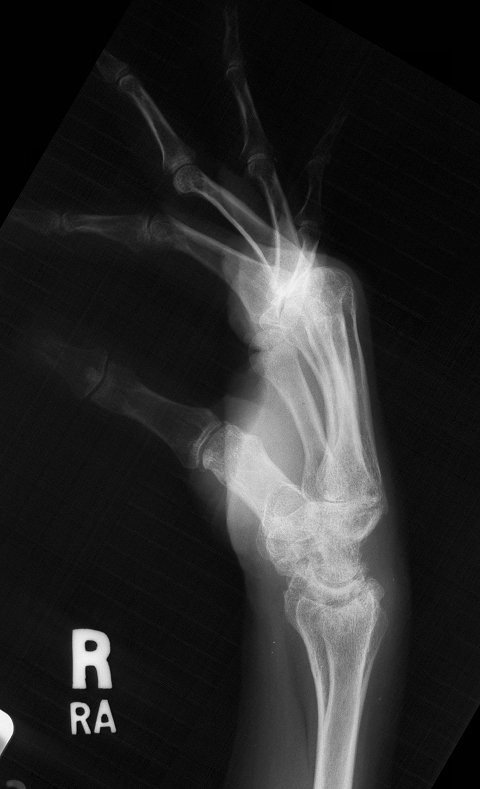

The radiolunate joint did not spontaneously fuse on this side, allowing a greater degree of ulnar translation of the carpus. Note the severe cystic carpal changes.